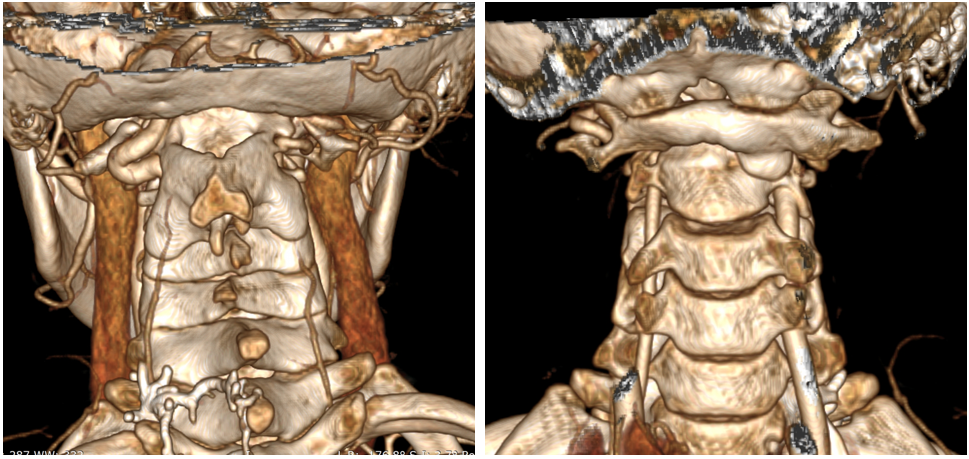

女,13岁,154cm,57kg

• 6个月前病人出现颈部活动受限,3个月前出现左手力弱

影像资料:

诊断:

• 齿状突小体

• 寰枢椎脱位

治疗:

• 后路关节松解寰枢椎复位内固定融合术

• 前路关节松解,后路寰枢椎复位内固定融合术

• 前路TARP技术

• 前路齿状突切除,后路内固定术